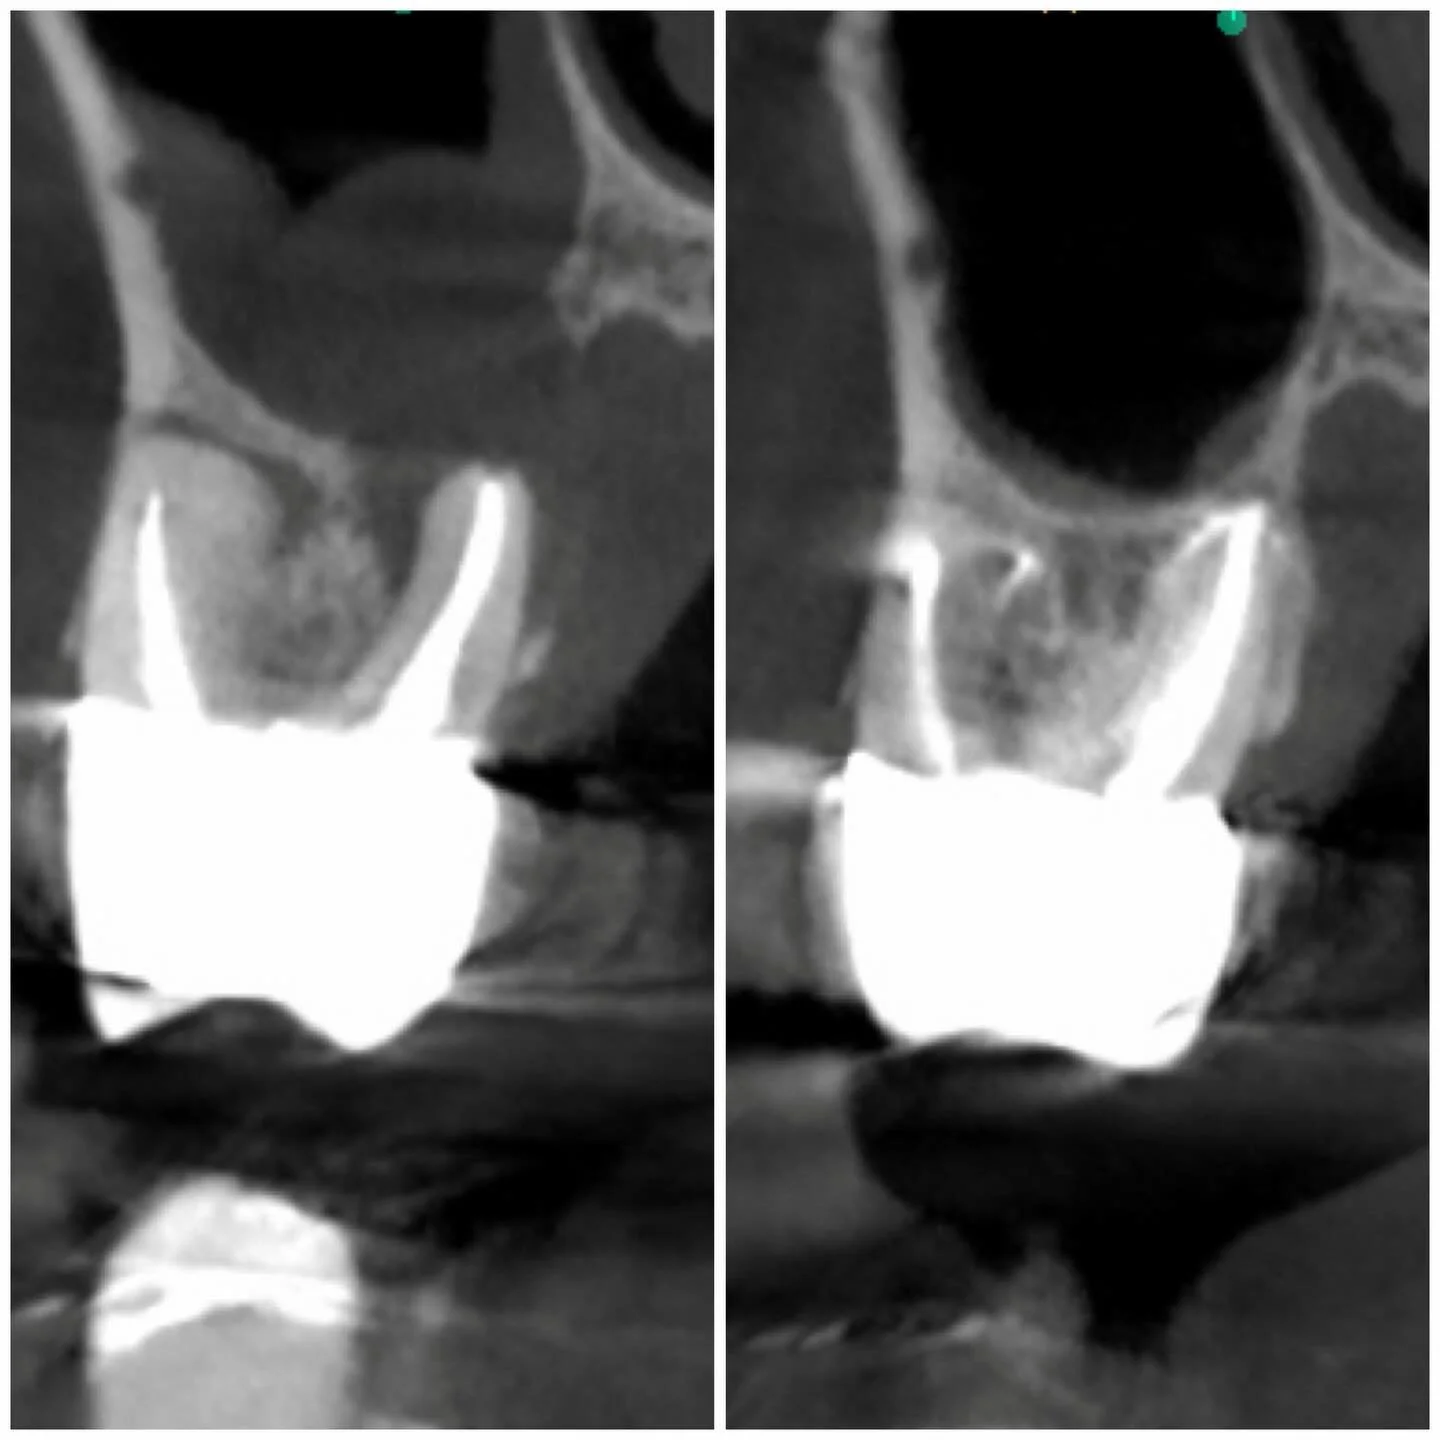

I am a board-certified endodontist with advanced specialty training and an academic interest in diagnostic reasoning, retreatment, and microsurgical endodontics. My work emphasizes CBCT-guided decision-making, interdisciplinary collaboration, and evidence-based care in complex clinical scenarios.